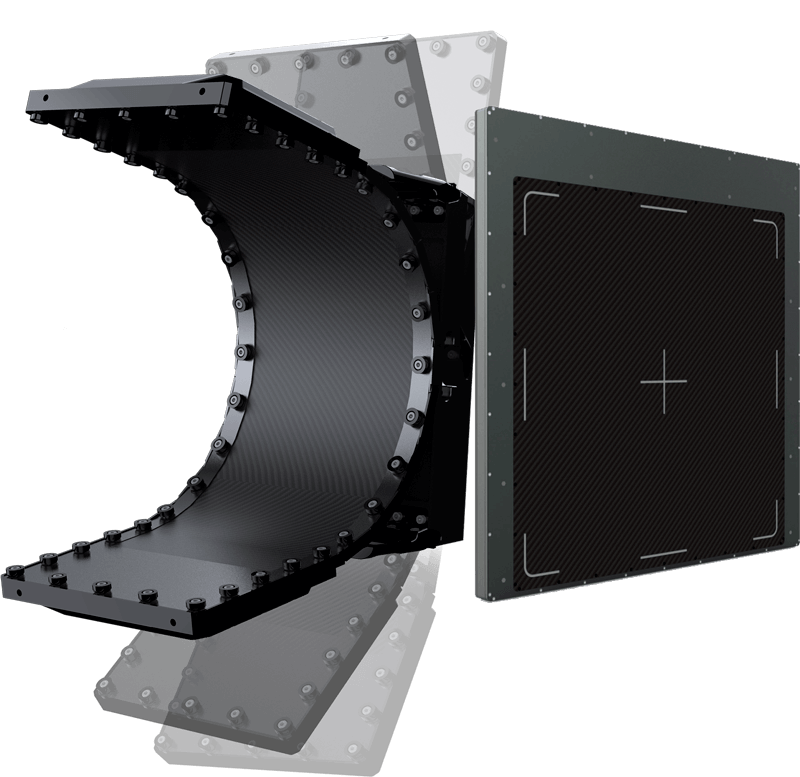

PROTECCIÓN PARA DETECTORES

Resistente, adaptable y confiable.

Protección con Grilla

Adaptado a Todas Tus Prácticas

Tres tipos de protección adaptados a tus necesidades. Protección de peso ideal para radiografía con carga, protección con ó sin grilla y contra impactos, resistentes y de bordes suaves.

- Adaptado para seguridad y todo tipo de industria.

- Muy resistentes y livianos.

- Tecnología curva innovadora.

- Rendimiento superior en sistemas mamográficos.

- El tamaño de píxel más pequeño: 65µm.

- Tecnología a-SE de alta definición.